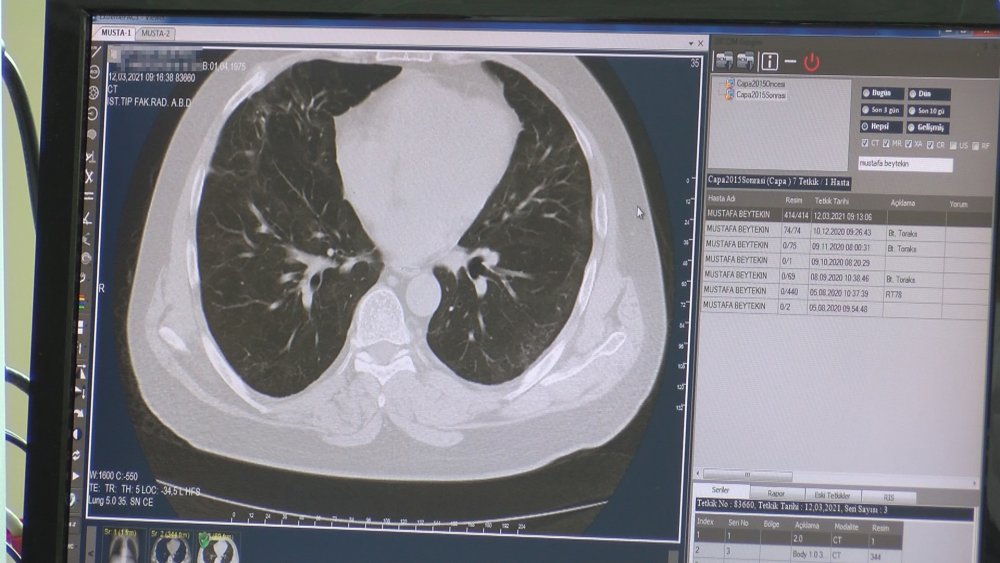

Son günlerde Cerrahpaşa Tıp Fakültesi özelinde ilk müracaat vaka sayılarında belirgin bir artış gözlemlediklerini söyleyen Prof. Dr. Gönen, "Yüzde 30 gibi bir artış var ilk başvurularda. Ama yaptığımız testlerdeki pozitiflik oranında henüz belirgin bir artış yok. Yatan hasta sayımızda da şu anda bir artış yok. Bugün itibariyle toplamda 38 hasta yatıyor. Yoğun bakım ünitemizde de 6 Kovid hastası var. Bizim ikinci pikte, yoğun bakımda hasta sayımız 55'e ulaşmıştı. Yoğun bakım kapasitemizi yükseltmiştik ve tamamı dolmuştu. Test pozitiflik oranlarımız ise son bir aydır, hatta 45 gündür yüzde 5 civarında seyrediyor" diye konuştu.

Salgının başladığı Mart 2020'den bugüne dek kendi merkezlerinde 180 binin üzerinde test yaptıklarını ve testlerden 21 bininin pozitif çıktığını belirten Prof. Dr. Gönen, şu bilgileri verdi.: "Bu da yüzde 11 gibi bir orana tekabül ediyor. Yani tüm pandemi boyunca test pozitiflik oranımız yüzde 11 civarında. Son 45 gündür yüzde 5 civarında seyretse de önümüzdeki günlerde artma potansiyeli olduğunu düşünüyorum. Çünkü ilk müracaatlarda ciddi bir artış var şu anda ve İstanbul genelinde baktığımızda, diğer hastanelerde de ciddi bir artış olduğunu biliyoruz. Diğer iller için de İstanbul için de geçişlerde mutlaka kontrol olması gerekiyor. Ayrıca bir de kafe ve restoranların dış mekana masa koyma sınırlamasında, belediyelerin biraz daha hoşgörülü davranması lazım. İnsanlar açık havada daha fazla zaman geçirebilir böylece."